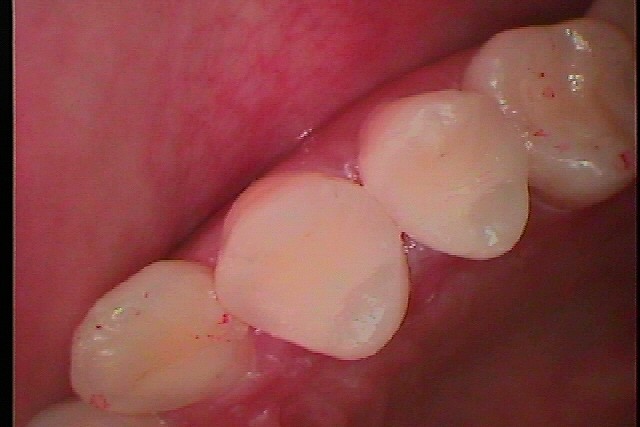

セレックセラミックにて修復しています

本来の歯を取り戻しました